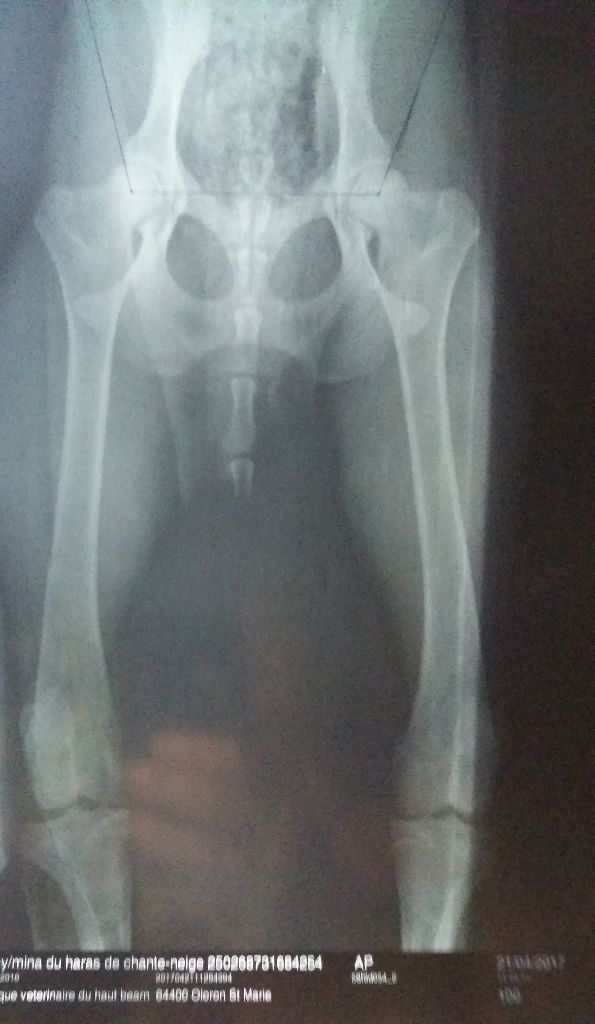

Contrôle dysplasie des hanches : exempte totalement A/A

Dentition : Complète en ciseaux Dysplasie des coudes : Aucun problème de coude constaté dans sa vie Dépistage dysplasie hanches : exempte dysplasie A/A (angles 105/108) |